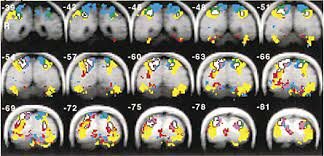

• SEIJI OGAWA (1990). Neurocientifico japonés

SEIJI OGAWA (1990). Neurocientifico japonés

Demostró que se podía seguir al milímetro la oxigenación de la hemoglobina eritrocítica a través de tomógrafos de resonancia magnética (RM, técnica de neuroimagen capaz de detectar los cambios fisiológicos ocurridos en el cerebro relacionados con procesos mentales) y, en consecuencia, también de forma indirecta el flujo sanguíneo cerebral. La conclusión era evidente: las regiones encefálicas mejor perfundidas probablemente sean las más activas